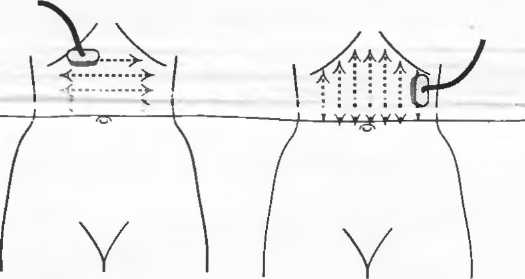

1. Подготовка

Пациент не должен пить и есть в течение 8 ч перед исследованием. Если жидкость необходима для предотвращения дегидратации, можно давать пациенту только воду. При острой симптоматике исследование можно проводить без подготовки. Детям, если позволяют клинические условия, пища и вода не даются в течение 3 ч до исследования.